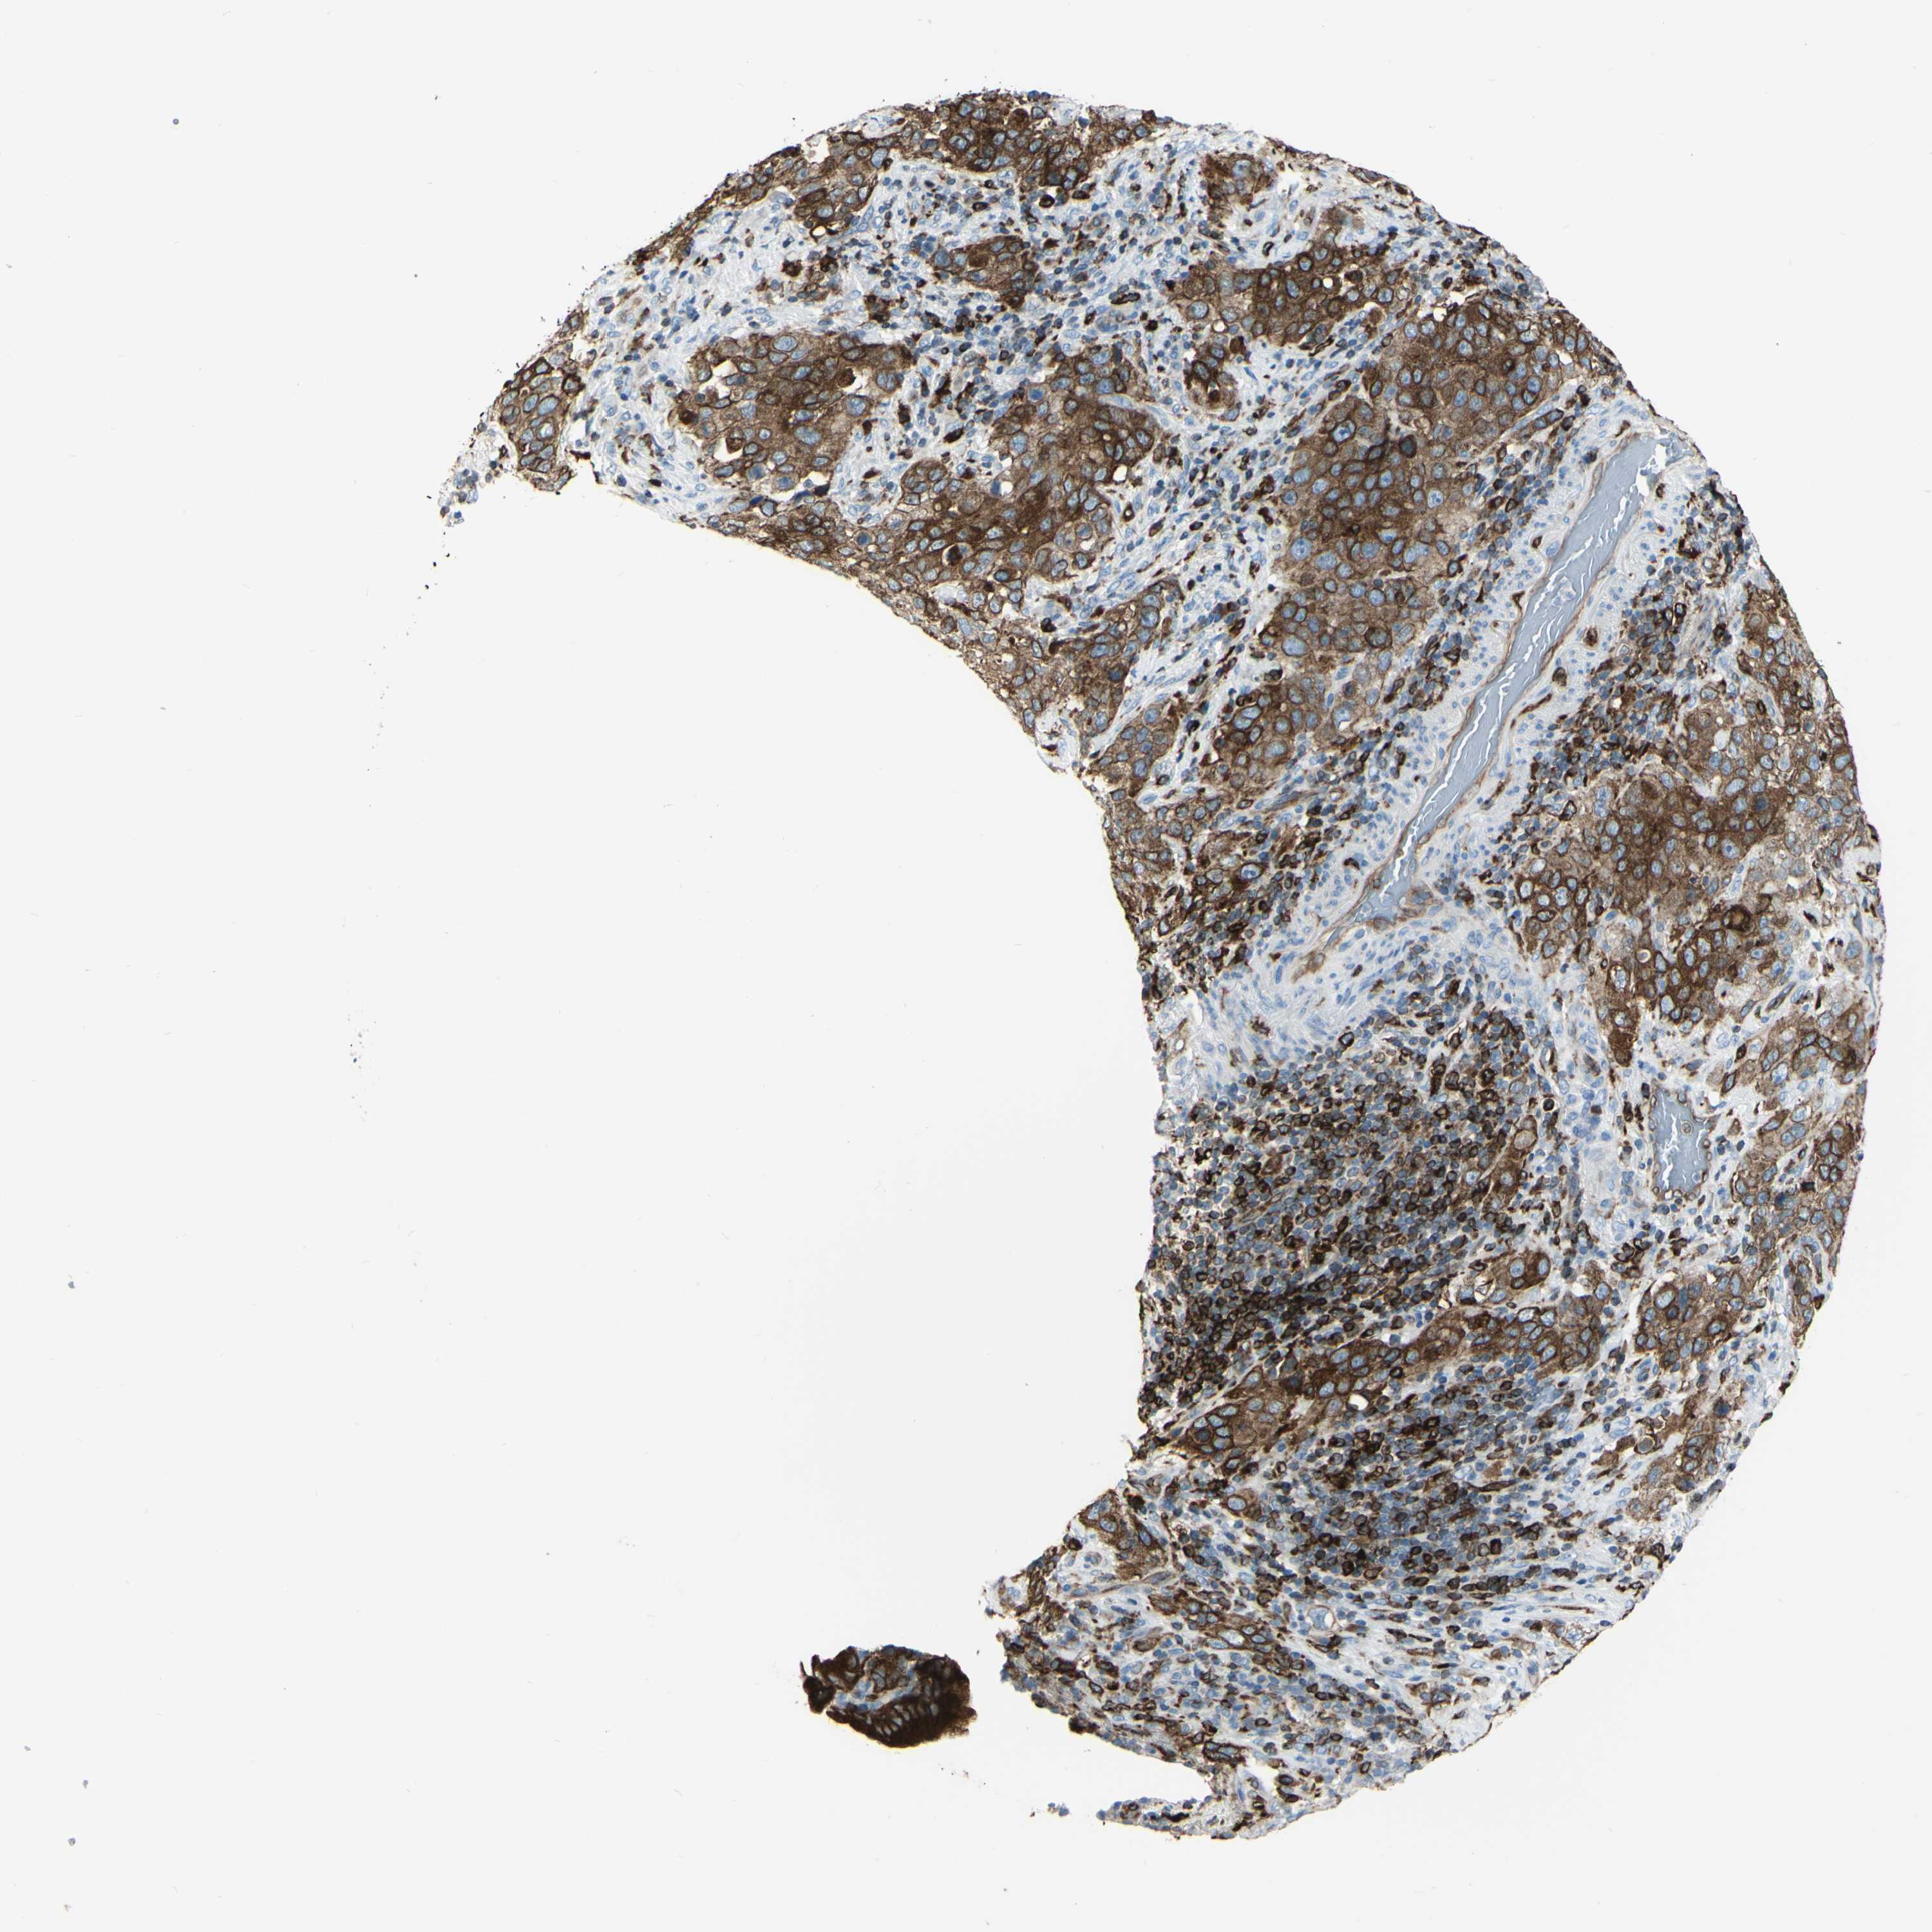

STOMACH CANCER - Protein expressioni

A mouse-over function shows sample information and annotation data. Click on an image to view it in a full screen mode. Samples can be filtered based on level of antibody staining by selecting one or several of the following categories: high, medium, low and not detected. The assay and annotation is described here.

Note that samples used for immunohistochemistry by the Human Protein Atlas do not correspond to samples in the TCGA dataset.

Antibody stainingi

Antibody staining in the annotated cell types in the current human tissue is reported as not detected, low, medium, or high, based on conventional immunohistochemistry profiling in selected tissues. This score is based on the combination of the staining intensity and fraction of stained cells.

Each image is clickable and will lead to virtual microscopy that enables deeper exploration of all samples and also displays staining intensity scores, fraction scores and subcellular localization as well as patient and tissue information for each sample.

Staining

High

Medium

Low

Not detected

Intensity

Strong

Moderate

Weak

Negative

Quantity

>75%

75%-25%

<25%

None

Location

Nuclear

Cytoplasmic/membranous

Cytoplasmic/membranous,nuclear

Adenocarcinoma, NOS

Adenocarcinoma, High grade